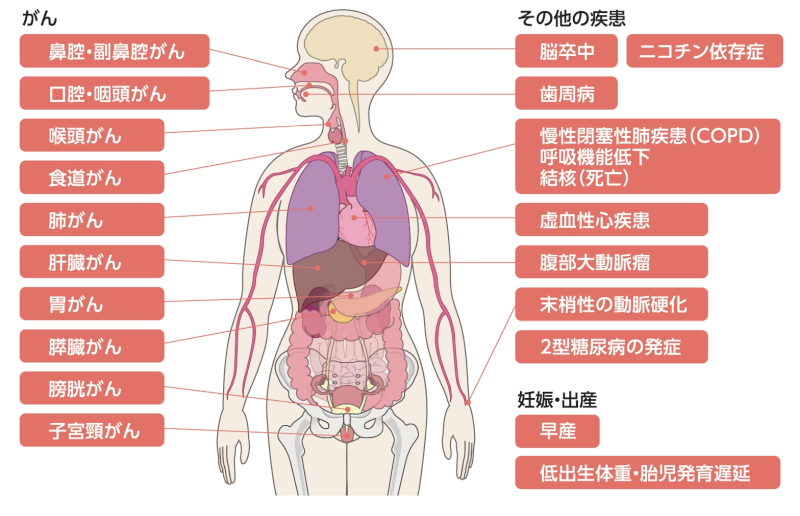

加熱式たばこ: 国立がん研究センター がん情報サービス 一般の方へ。

アイコスに害はある?加熱式タバコの発がん性や有害性についての噂を調査BEYOND VAPE JAPAN 公式。

シケモクを吸うと死ぬ?発がん性物質のリスクや健康被害の影響とはコンビニなう。

シケモクを吸うと死ぬ?発がん性物質のリスクや健康被害の影響とはコンビニなう。